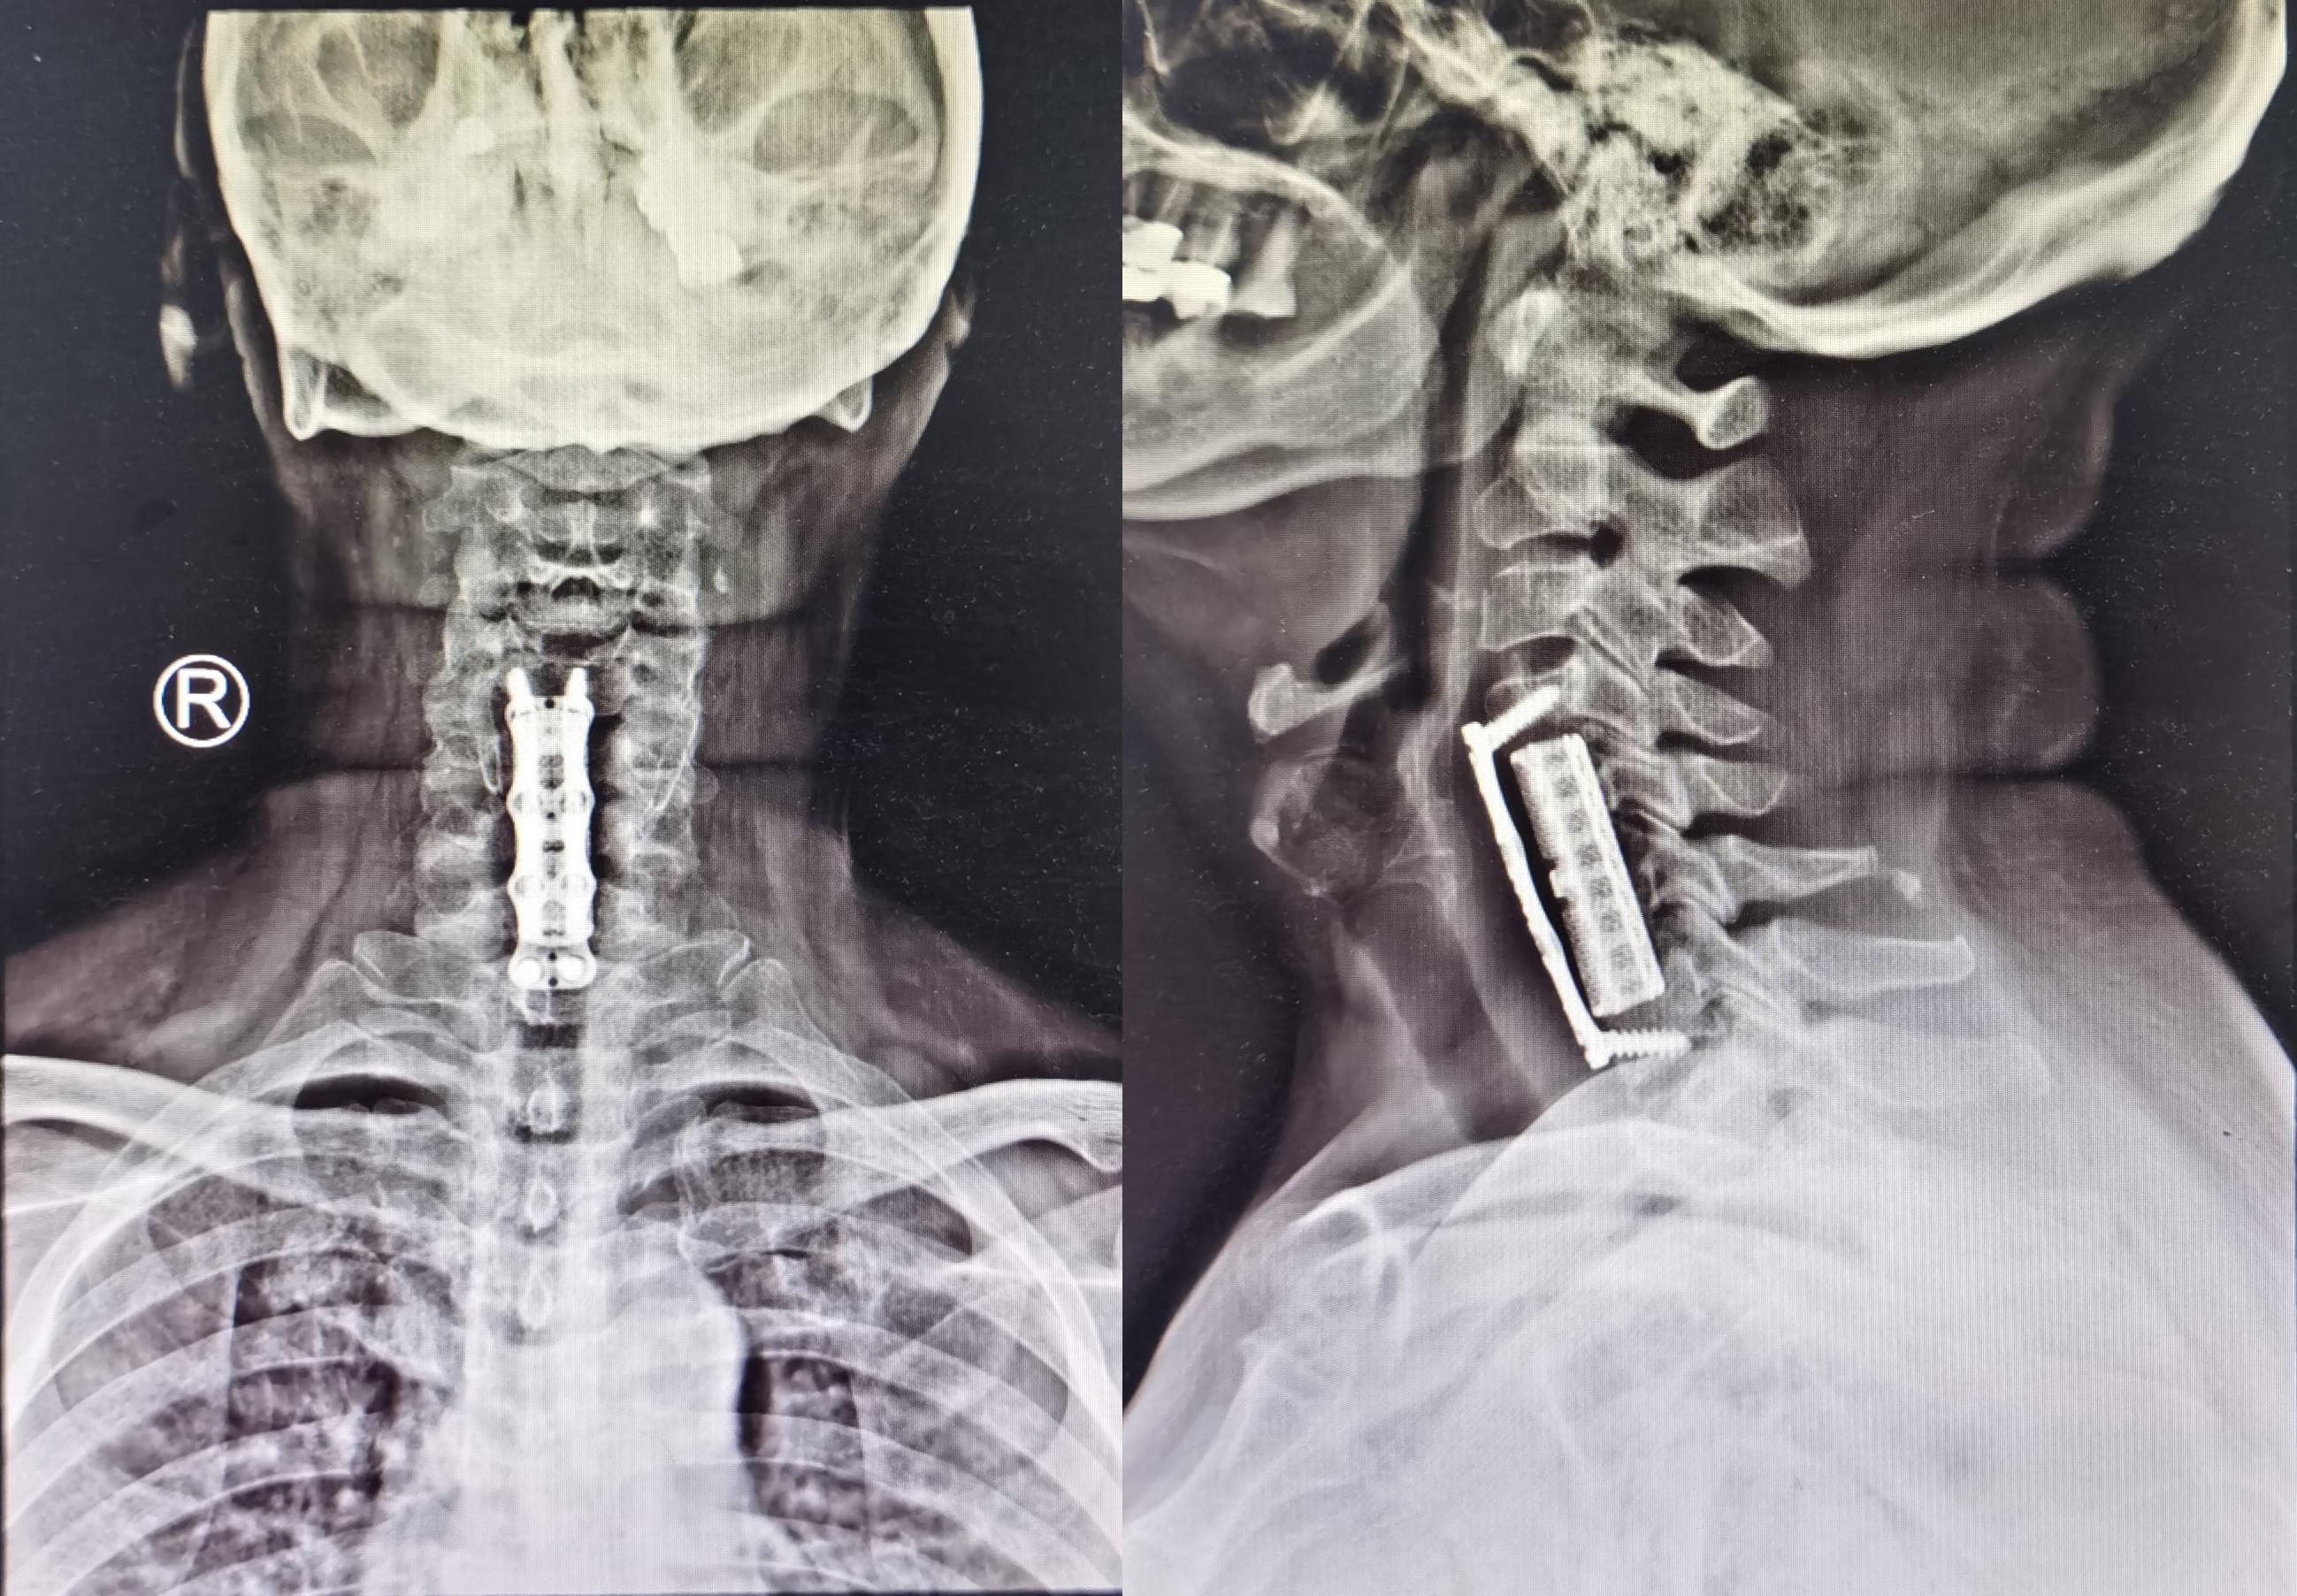

2020年8月4日(即第一次行前路颈5-6椎间盘切除椎间植骨融合内固定术后第114天),再次行颈椎前路颈5、颈6锥体次全切、人工锥体钛板螺钉内固定术,2020年8月5日(即第二次颈椎病术后第1天)复查颈椎平片及颈椎CT示椎管狭窄解除,人工椎体位置良好( 图-6、图-7 )。

图-6: 2020年8月5日颈椎平片

图-7: 2020年8月5日颈椎CT